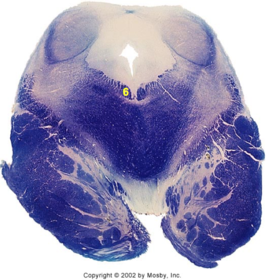

| Superior vestibular nucleus | |

| Medial lemniscus | |

| Trapezoid body | |

| Ventral trigeminothalamic tract | |

| Superior olive | |

| Longitudinal pontine fibers (corticospinal tract) | |

| Transverse pontine fibers (dark fibers) | |

| Pontine nuclei (pale) | |

| Central tegmental tract | |

| ALS | |

| Medial longitudinal fasciculus | |

| Middle cerebellar peduncle | |

| Superior cerebellar peduncle | |

| Anterior spinocerebellar tract | |

| Principle nucleus of V | |

| Mesencephalic V tract | |

| Trigeminal root fibers | |

| Motor nucleus of V | |

| Cerebellar vermis | |

| Lateral lemniscus | |

| Longitudinal pontine fibers (c-spinal, c-bulbar, c-pontine fibers) | |

| Transverse pontine fibers (dark) | |